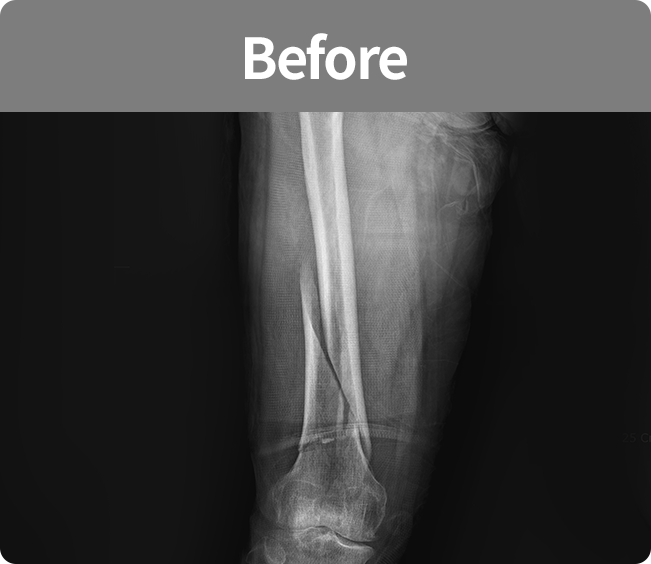

골절 고정술

부러진 뼈를 해부학적 위치로 정확하게 맞춘 뒤,

뼈가 안정적으로 붙을 수 있도록 금속판, 나사, 핀 등을 이용해 고정하는 수술

(내고정술, 외고정술)